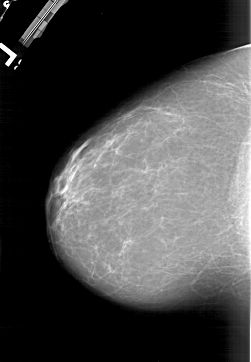

A_1177_1.RIGHT_MLO

RIGHT_CC LINES 5881 PIXELS_PER_LINE 4156 BITS_PER_PIXEL 12 RESOLUTION 43.5 OVERLAY